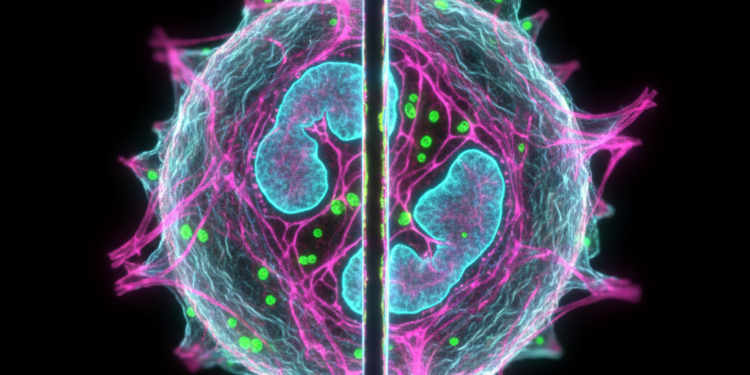

O estudo das células orais, como os queratinócitos, fibroblastos e células imunes, é fundamental para compreender várias condições de saúde bucal. Os cortes ópticos gerados pela microscopia confocal permitem que os cientistas investiguem a morfologia, organização e comportamento dessas células de maneira detalhada.

A capacidade de visualizar cortes múltiplos em 3D tem facilitado a identificação precoce de doenças bucais, como lesões neoplásicas e infecções. As imagens 3D celulares extraídas por meio da microscopia confocal proporcionam insights sobre como as células interagem entre si e podem servir como indicadores de progressão de doenças.

Após a captura de cortes ópticos pela microscopia confocal, as imagens podem ser processadas por softwares especializados para criar reconstruções tridimensionais. Este processo envolve a montagem de múltiplas camadas de imagens em um único modelo 3D, permitindo análises mais profundas e detalhadas.

Os softwares de reconstrução são projetados para combinar as imagens obtidas em diferentes planos focais, resultando em um modelo tridimensional. Com essa tecnologia, pesquisadores podem manipular a visualização, rotacionando e ampliando o modelo para examinar detalhes específicos. Isso é essencial para estudos em citologia e pode ser acessado em detalhes em nosso site sobre citologia.